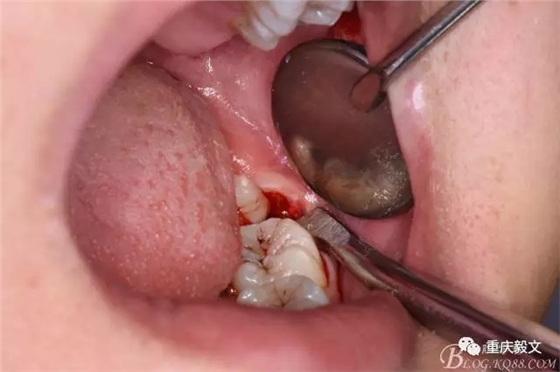

圖7.高速渦輪鉆分牙

圖8.先從頸部橫斷38

圖9.再把38牙冠近遠(yuǎn)中縱斷